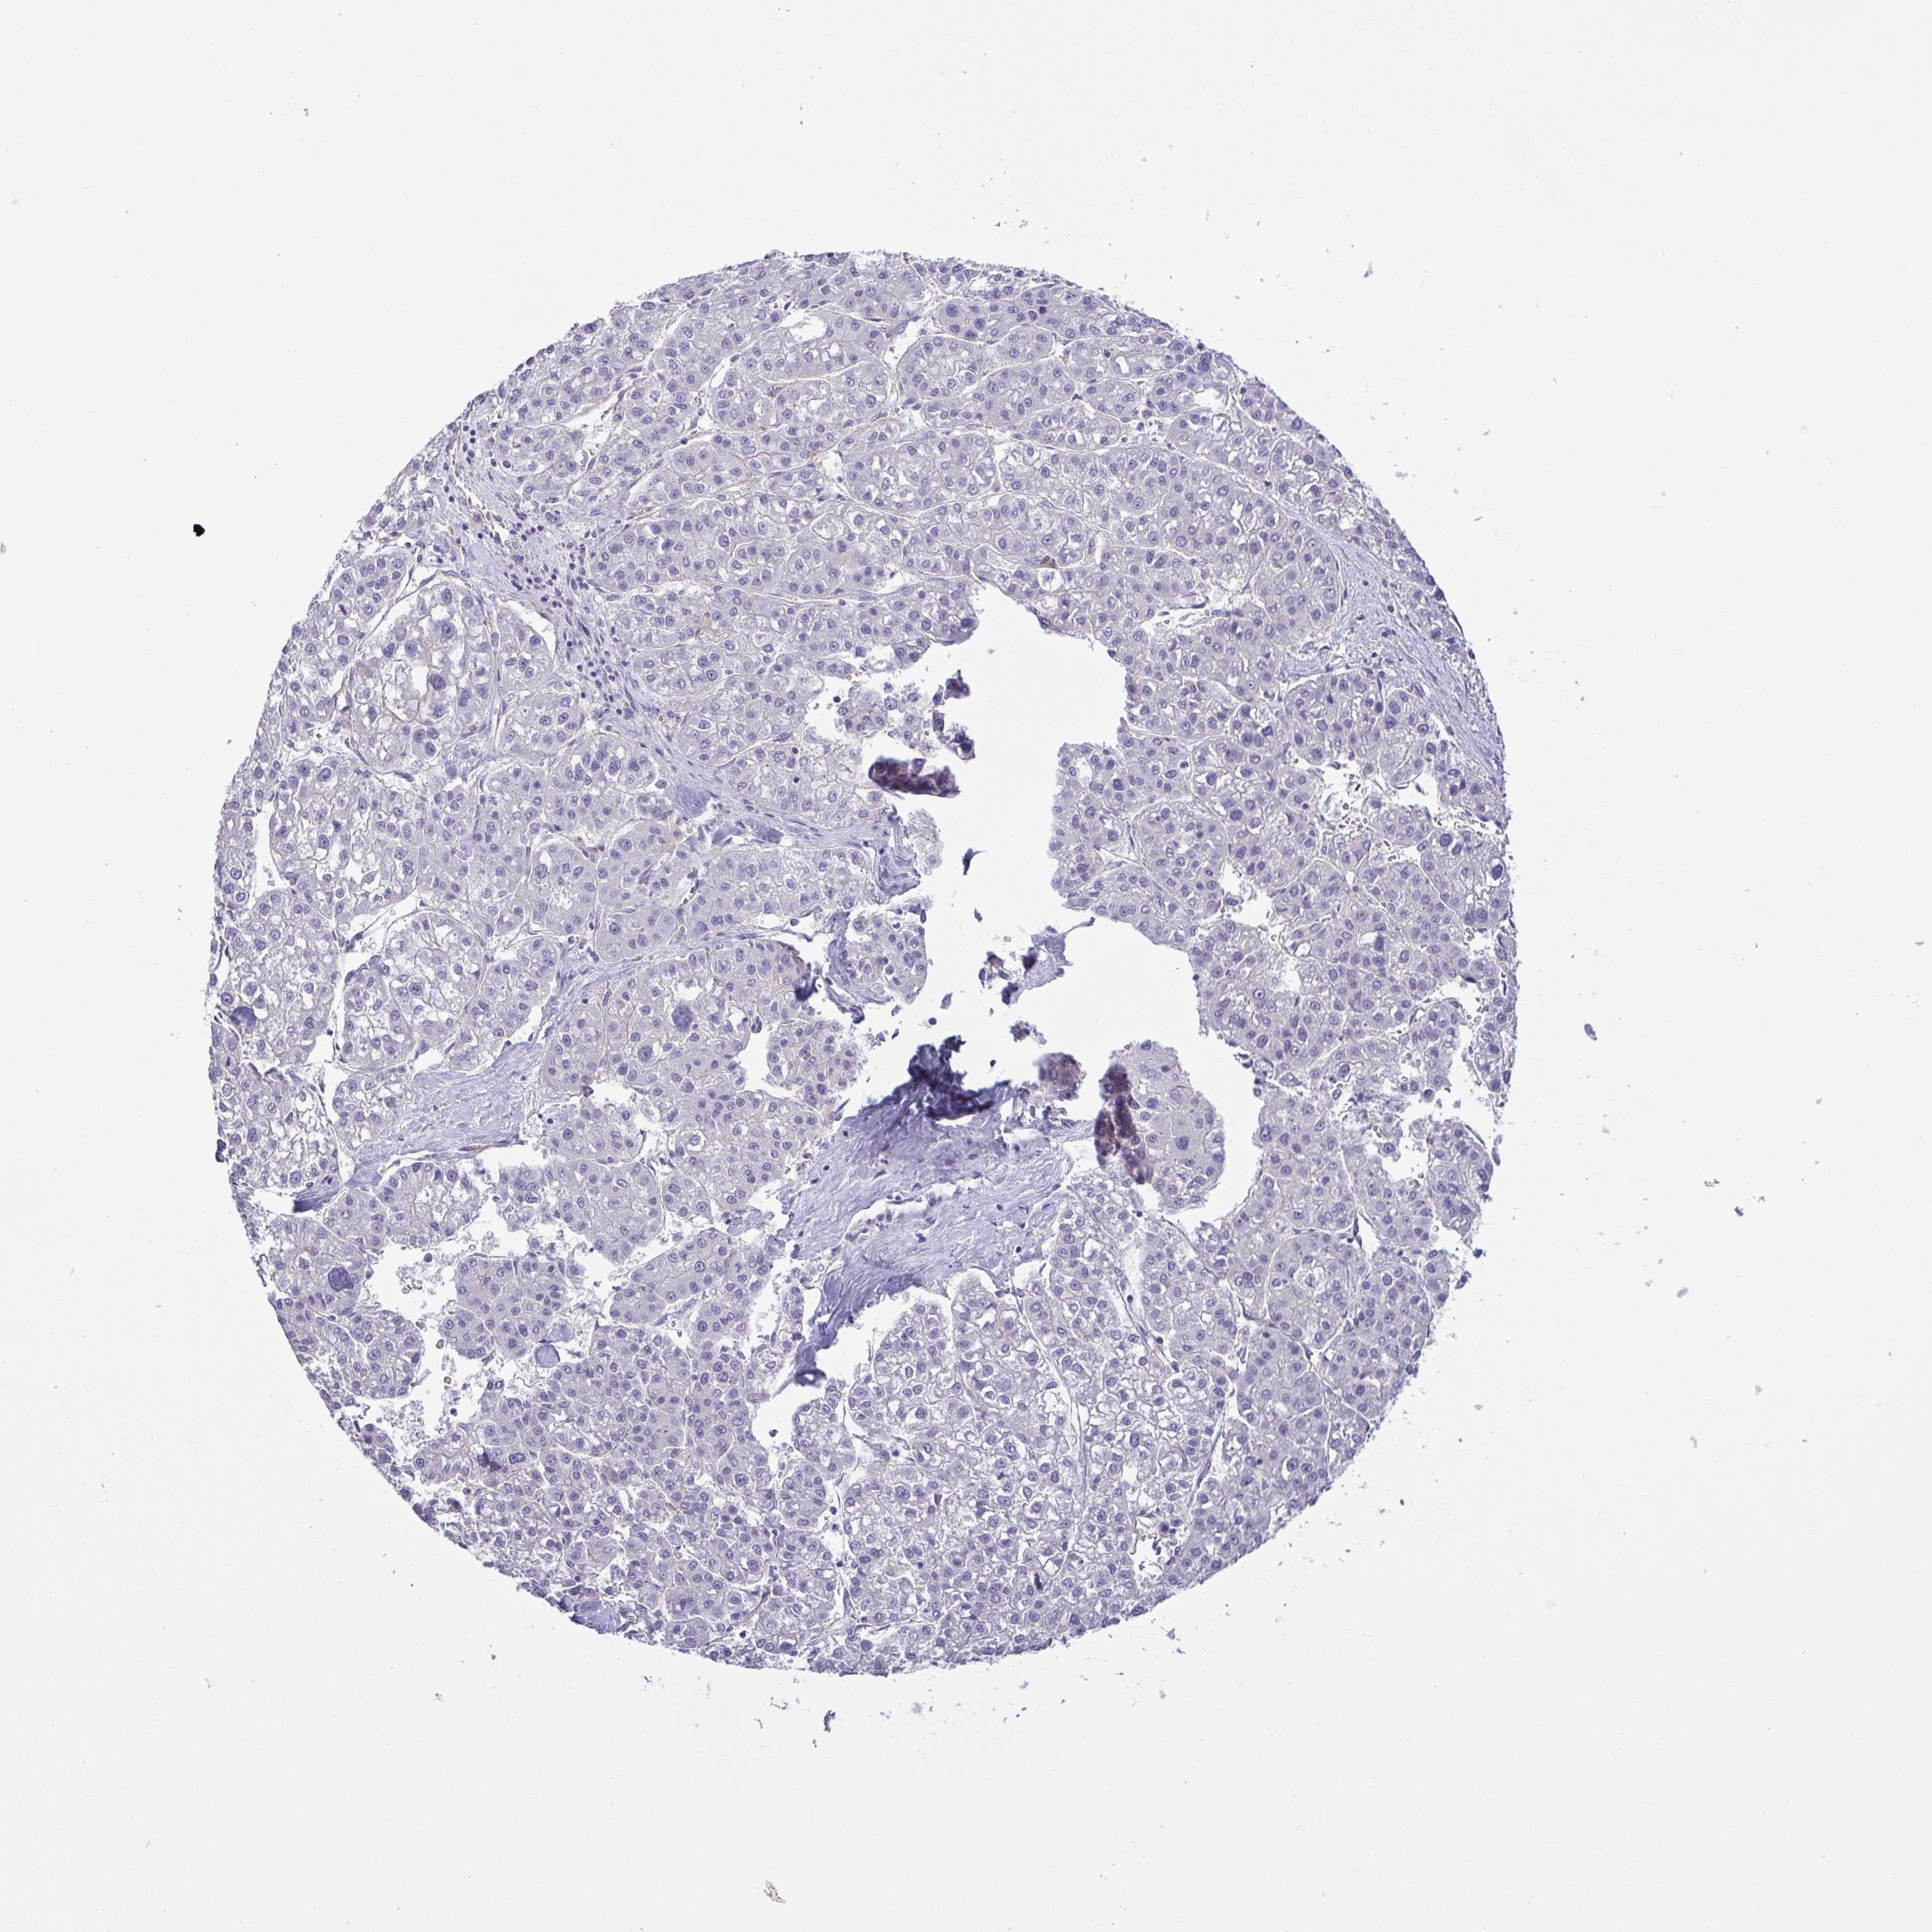

LIVER CANCER - Protein expressioni

A mouse-over function shows sample information and annotation data. Click on an image to view it in a full screen mode. Samples can be filtered based on level of antibody staining by selecting one or several of the following categories: high, medium, low and not detected. The assay and annotation is described here.

Note that samples used for immunohistochemistry by the Human Protein Atlas do not correspond to samples in the TCGA dataset.

Antibody stainingi

Antibody staining in the annotated cell types in the current human tissue is reported as not detected, low, medium, or high, based on conventional immunohistochemistry profiling in selected tissues. This score is based on the combination of the staining intensity and fraction of stained cells.

Each image is clickable and will lead to virtual microscopy that enables deeper exploration of all samples and also displays staining intensity scores, fraction scores and subcellular localization as well as patient and tissue information for each sample.

Antibody HPA023871

Antibody HPA052645

Staining

High

Medium

Low

Not detected

Intensity

Strong

Moderate

Weak

Negative

Quantity

>75%

75%-25%

<25%

None

Location

Nuclear

Cytoplasmic/membranous

Cytoplasmic/membranous,nuclear

Cholangiocarcinoma

Carcinoma, Hepatocellular, NOS